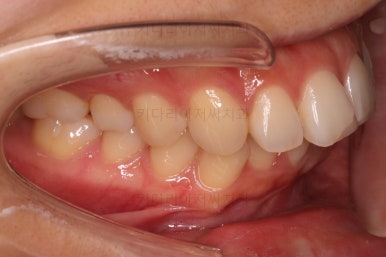

마찬가지로 부산연산동교정치과 초진 시 입안의 모습입니다.

눈에 띄는 것은 윗니 안쪽 치아 하나가 아예 입천장쪽으로 나서 매우 삐뚤어요.

저렇게 삼각혁으로 배치되어 있는 치아는 셋 중 하나는 꼭 썩어요.

셋 사이에 음식물이 잘 끼고 양치가 힘들기 때문이죠.

아래 앞니도 삐뚤한 편이었고 아래 앞니가 불쑥 위로 올라와 있어서 이를 악 다물면 위아래 앞니가 많이 겹치는 "과개교합" 패턴이 나타나요.

윗니가 전반적으로 아랫니보다 앞에 나와 있어서 2급 부정교합에 윗니만 튀어나온 양상이고 이 때문에 윗니 앞니가 다치고 부러졌따가 떼운 흔적이 보이네요.